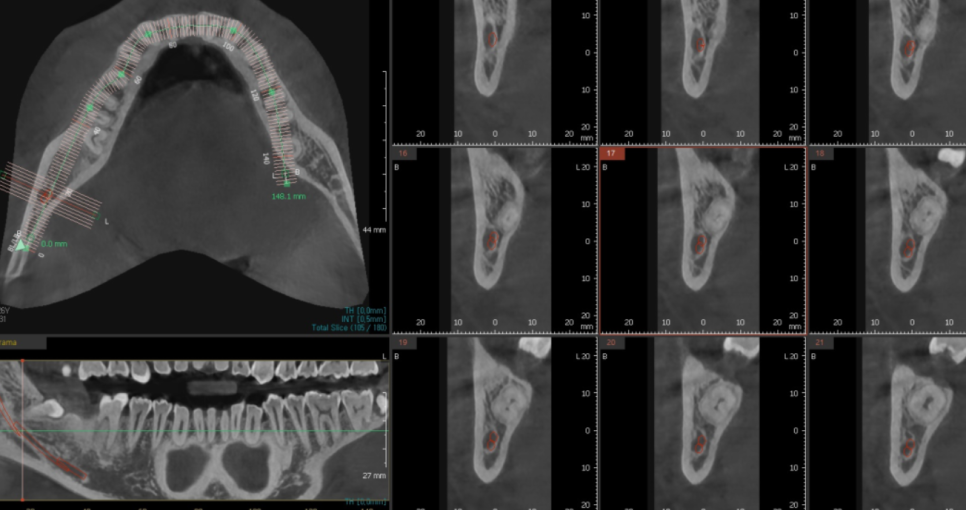

230731

이 문제도 CT를 통해 분석을 잘하면

문제가 없어요.